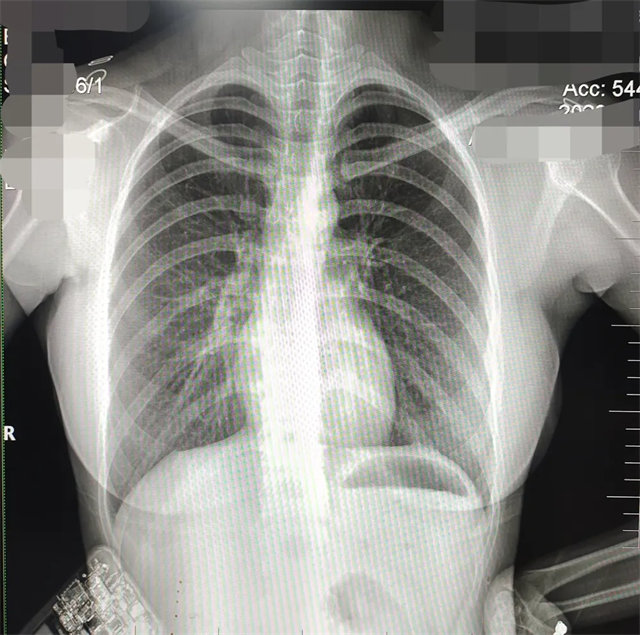

缺陷:雙側胸鎖關節(jié)不對稱,且有手機顯影。

解決:去除手機后,使患者左側緊貼成像件曝光。